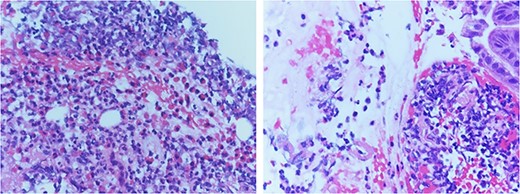

The pathology report of the intraoperative biopsy showed eosinophilic gastritis (>20 eosinophils per high power field) (Fig. 2) and Helicobacter Pylori testing was negative. An upper GI study performed postoperative Day 5 showed no evidence of a leak from the primary repair in the stomach, and the patient was started on a clear liquid diet. The patient was subsequently discharged on postoperative Day 7. The patient was seen in the surgery clinic on postoperative Day 13 and was recovering appropriately. The patient followed up with the gastroenterology clinic and was placed on a 6-food elimination diet and proton pump inhibitor with the plan for a follow-up outpatient EGD.

Pathology review demonstrated increased eosinophil infiltration (>20 eosinophils per 40 x High Power Field) in submucosa with fragments of gastric mucosa, consistent with eosinophilic gastritis.